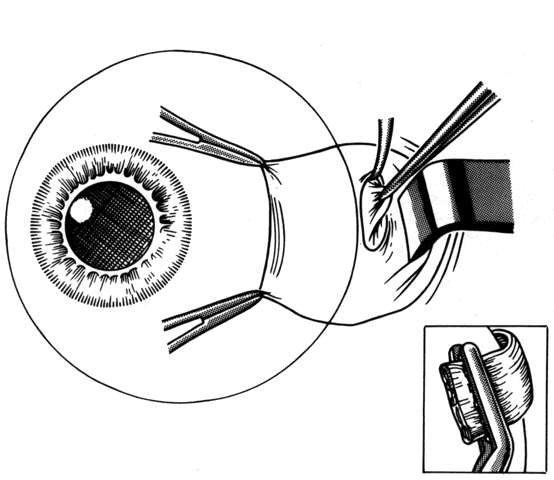

After the incision has been made and the dissection through Tenon's capsule has been completed to the surface of the sclera, muscle hooks are passed behind the rectus muscle to identify the insertion of the muscle. Once the muscle has been “hooked,” there is improved control of the globe. This will facilitate the blunt and sharp dissection that will be needed to reflect the conjunctiva over the tendon of the muscle (Fig. 15). Sharp dissection beneath the conjunctiva is used to separate fibrous tissue and restrictive bands from the surface of the muscle capsule and the sclera (Figs. 16 and 17). Frequently it will be necessary to remove small amounts of tissue to visualize the area of contact of the muscle insertion (Fig. 18).

Fig. 15. A Jameson muscle hook is under the insertion of a previously recessed horizontal rectus muscle. The insertion is cleared of any residual adhesive bands and scar tissue.

Fig. 16. Wescott scissors and toothed forceps are used to reflect conjunctiva (top) for removal of subconjunctival fibrous tissue (bottom).